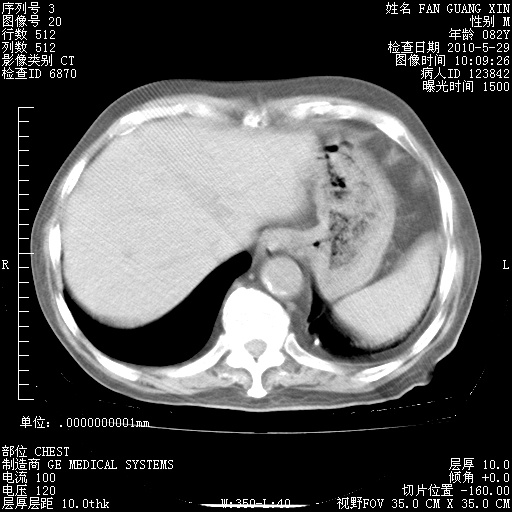

再治疗10天后的肺部CT 纵膈窗

阅读此次胸部CT,肺间质渗出性改变较入院时有吸收。目前从体温、白细胞、中性分叶明显增高,肯定存在细菌感染(发生医院感染哦,若无消化道及泌尿系统等感染的依据,肺部感染可能大)。若你院头孢哌酮舒巴坦钠耐药率较高,同意你的方案,若48小时体温仍高,可考虑使用碳青霉稀类抗菌药物,同时可予超声雾化、注意滴数时加大液体量。白蛋白33.30g/L较低哦,需加强营养等支持治疗。